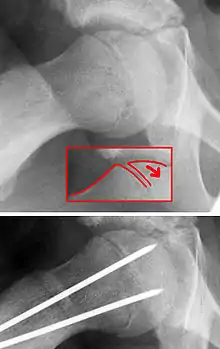

De hecho, el término epífisis capitel femoral deslizada es una denominación inexacta, ya que la epífisis (parte final de un hueso) permanece en su posición anatómica normal en el acetábulo de la cadera. En realidad, lo que se desliza en sentido anterior con rotación externa es la metáfisis (parte del cuello del hueso).

La SCFE es una fractura Salter-Harris de tipo 1 a través del cartílago de crecimiento femoral proximal.[8]

La enfermedad SCFE, se puede tratar con clavos externos in situ o con clavos y reducción abiertos.[14]